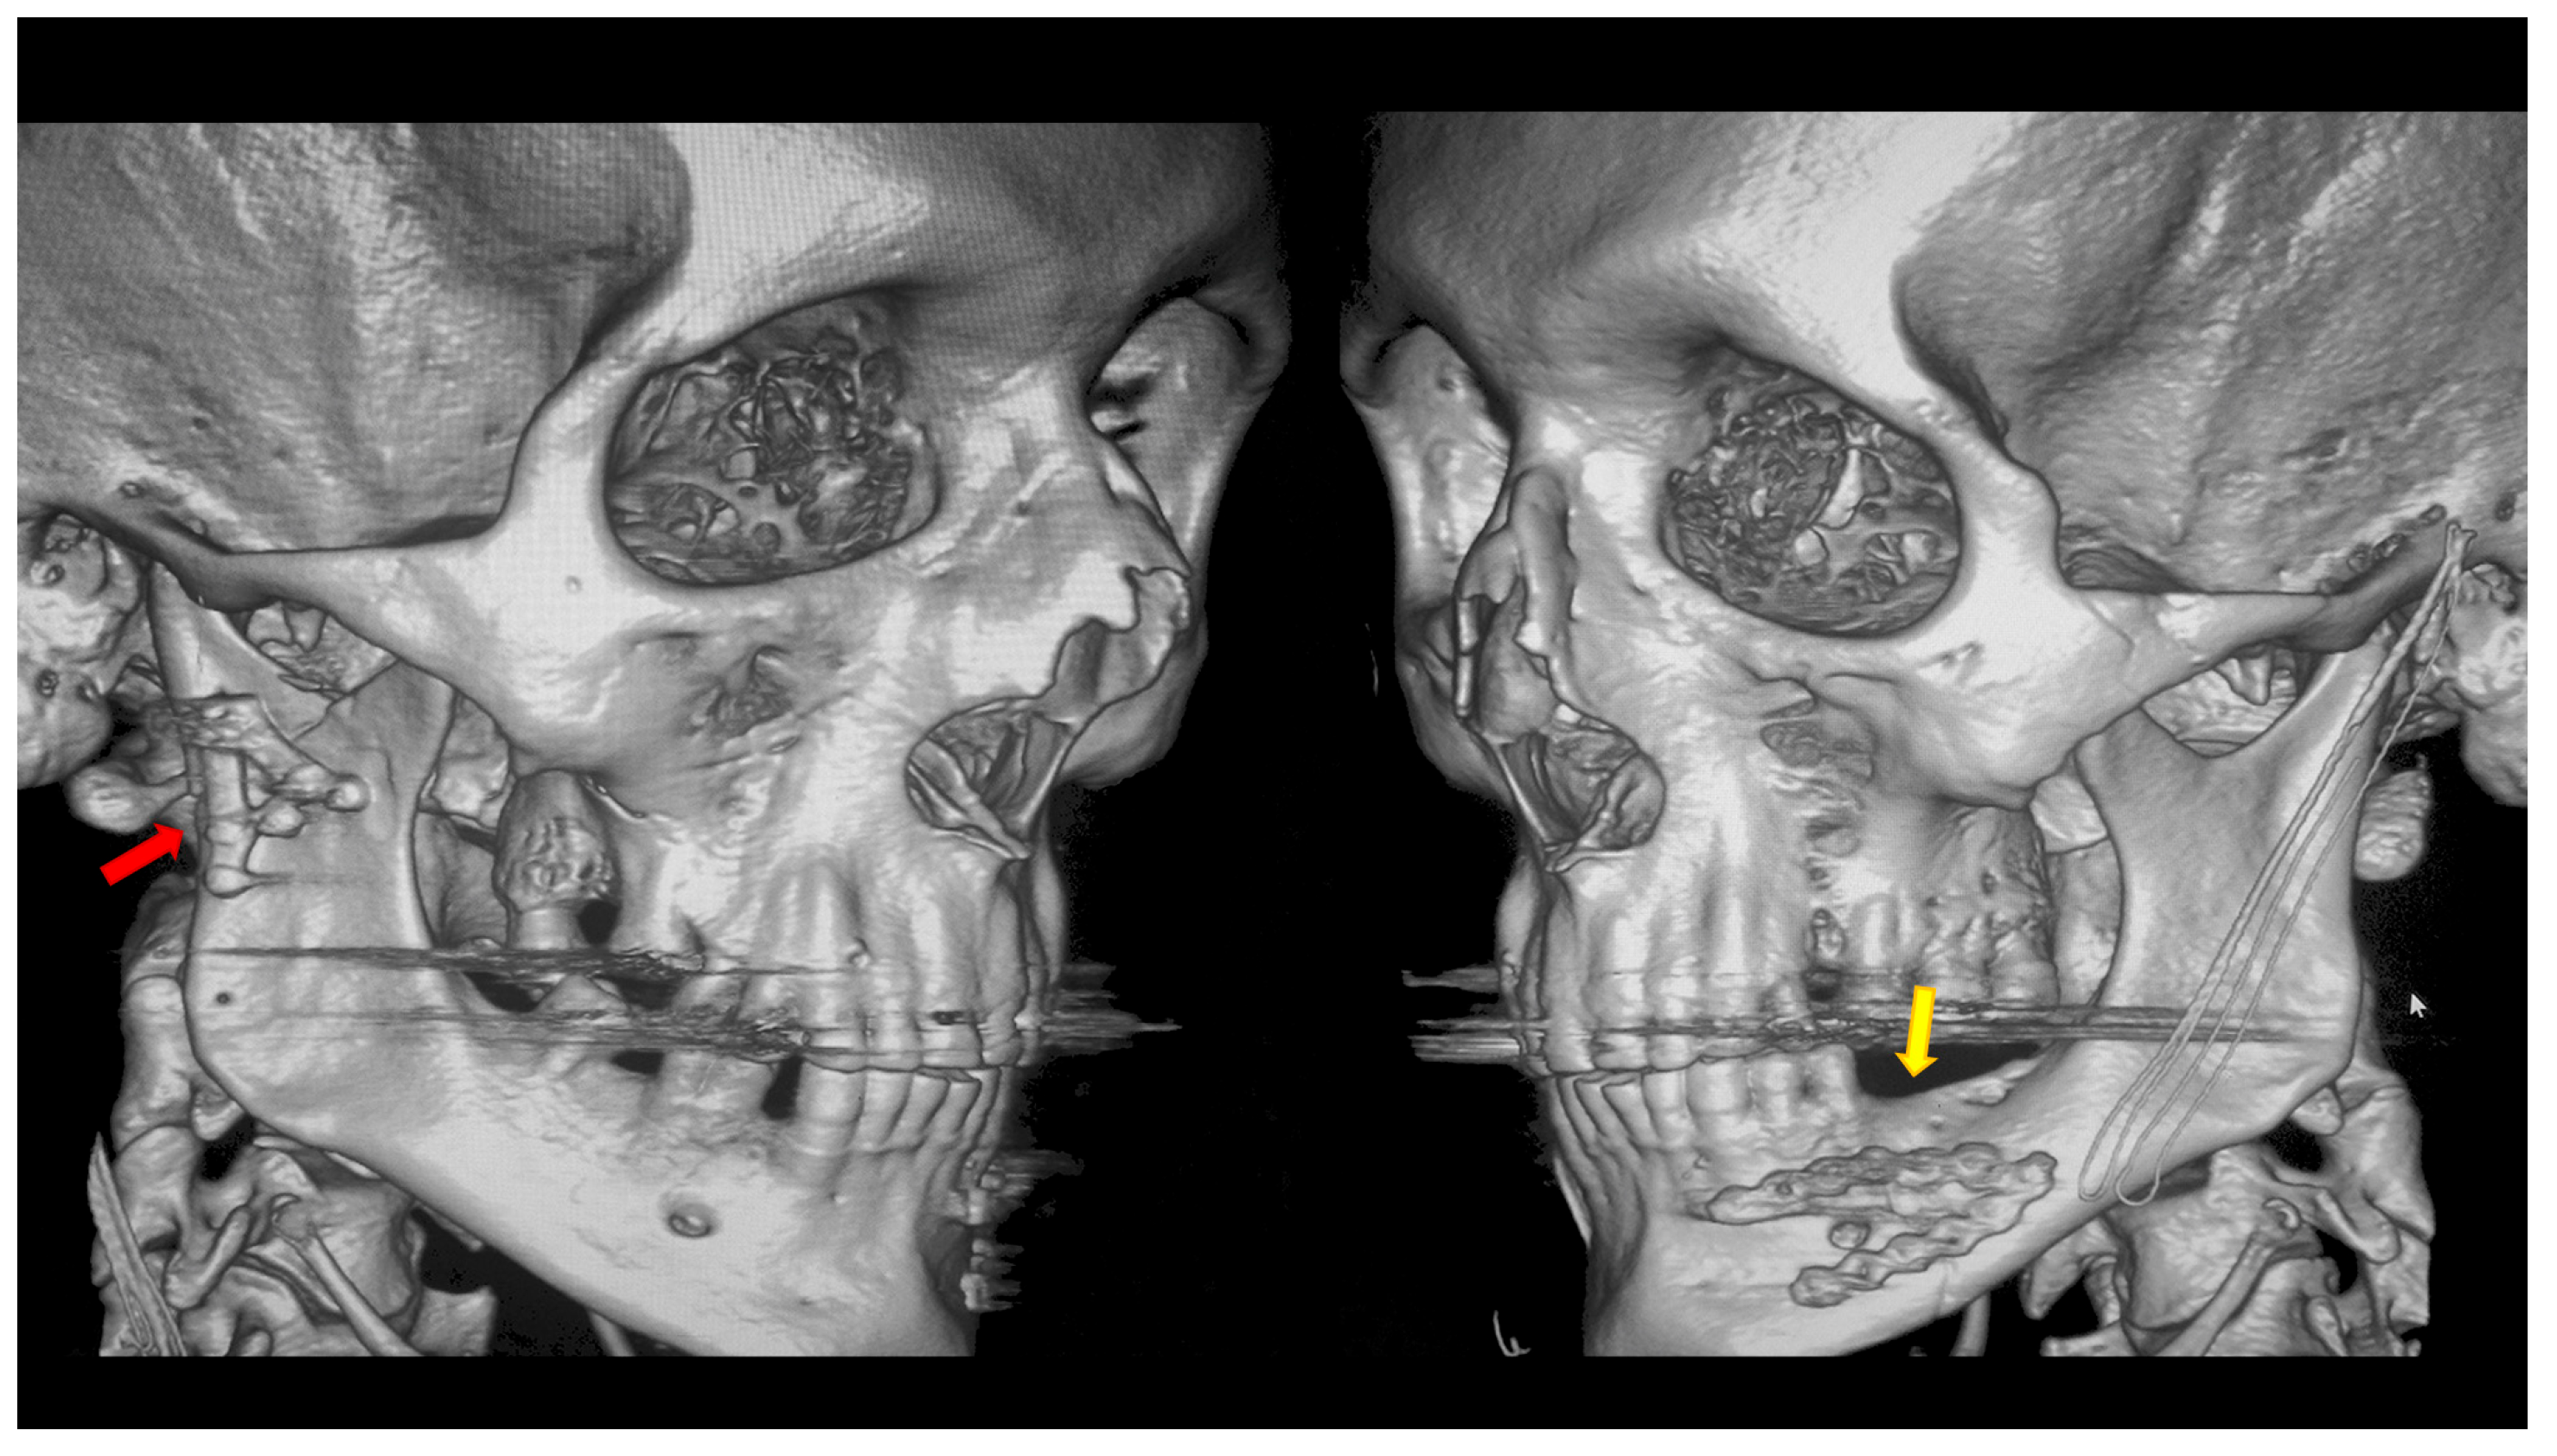

| Fracture diagnosis | CHF A | 359 | 0.56% | 0% | 0% | 0% | p = 0.671 |

| CHF B | 6.13% | 0.84% | 0.56% | 0% | |||

| CHF C | 16.43% | 5.57% | 5.57% | 1.11% | |||

| High—neck | 1.39% | 0.84% | 1.11% | 0.28% | |||

| Low—neck | 6.41% | 1.11% | 2.23% | 0.28% | |||

| Basal | 31.75% | 8.36% | 7.80% | 1.67% | |||